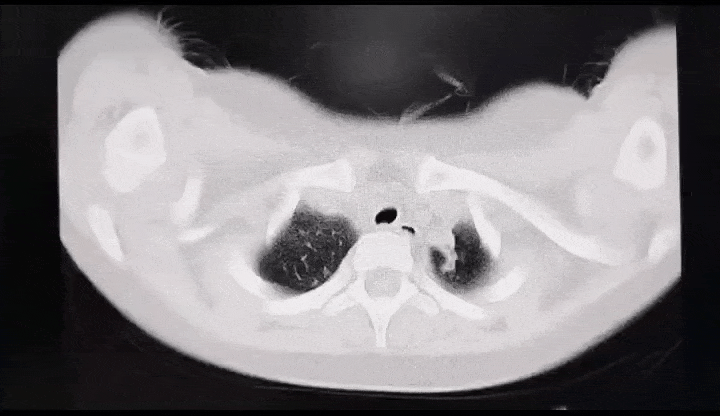

支原体肺炎的影像学表现。图源:深圳卫健委

有的支原体肺炎患儿,肺部影像上显示有一片白色,大多是一个肺叶或一个肺段感染所致,主要是由于气道阻塞物或肺内炎性渗出引起的,但其他的肺叶大多数都是正常的,这和医学上所说的“白肺”是两个概念。

通过拍背排痰、药物祛痰、支气管镜治疗等手段,患儿可以在较短时间内治愈。